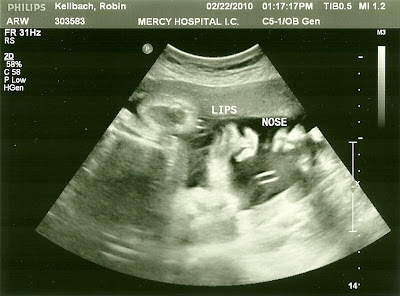

32 week ultrasound

We had our 3rd ultrasound today. This was the later one we had to have to determine if I still had a low lying placenta. As far as the tech could tell, the placenta had moved to the side! Yippee! We still need confirmation from the radiologist and my doctor, but it sounds like it will be pretty good news.

As usual it was wonderful to see our little girl on the screen. (We confirmed again and indeed it is still a little girl). Her nose was right up to the placenta, so it was hard to get any good face shots, even with the 3d ultrasound. Her hand was up by her forehead for most of the ultrasound. She looks like a total cutie. Of course, she reminds me of Isabella. Jeff thinks her nose is a little different. Her estimated weight right now is 4 lbs 15 oz. Her due date came in as 4/10, three days earlier than her official due date.

The just printed out photos and didn't give us a cd or anything, so I scanned them in, but I don't think they came out too clearly. The 3D images look like a blob at first, but if you adjust your eyes, you can see her face.